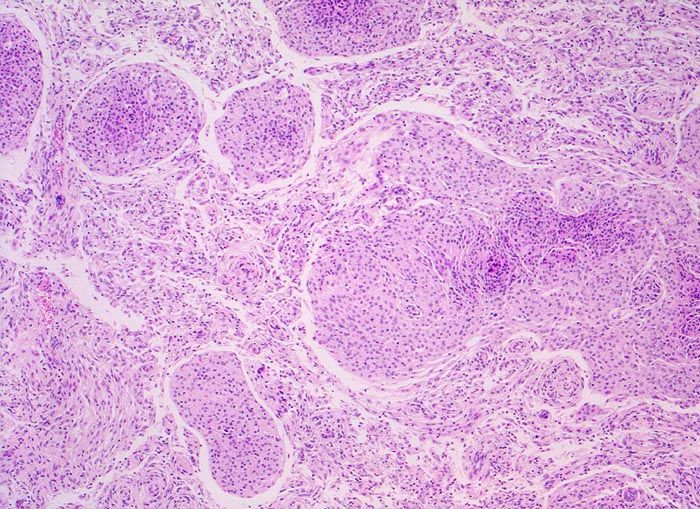

Das Meningeom zeigt ein grosses Spektrum histologischer Varianten mit sehr unterschiedlicher Morphologie. Am häufigsten sind meningotheliale (ihr Präparat), transitionale und fibroblastische Meningeome. Typisch für das meningotheliale Meningeom sind dicht gepackte Zellen mit unscharfen Zytoplasmagrenzen, Wirbelbildungen und Kerne mit intranukleären Vakuolen. Ferner finden sich konzentrische Verkalkungen in Form von Psammomkörperchen (> 255).

• Kugelige Tumorzellverbände mit Ausbildung von typischen konzentrischen zwiebelschalenartigen Formationen und parallele Bündel spindeliger Zellen.

• Tumorzellen mit ovalen Kernen ohne Atypien und reichlich Zytoplasma. Keine Mitosen.

• Psammomkörperchen (konzentrisch geschichtete Verkalkungen).